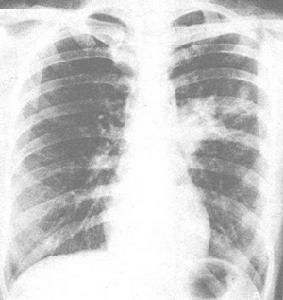

任何年齡都可發病,25-40歲是好發年齡。多為年青女性,發病隱襲,低熱(1-2周)、體重下降、衰弱、胸痛、肌肉麻木、厭食和陣發性夜間乾咳、咳少量玻璃透明狀黏稠痰、氣喘(嚴重者可呈哮喘持續狀態)及心血管系統和神經系統受累的表現。體格檢查,可聞及粗的濕性囉音、乾囉音和哮喘音。可有全身的淋巴結和肝脾腫大,兒童多見。

疾病早期(2周)典型表現為肺泡、間質、支氣管周圍和血管周圍間隔組織細胞炎症,肺組織結構正常,在肺組織上可見微結節,症狀發作1-3個月後,未經治療的病人肺泡和間質內有嗜酸粒細胞和組織細胞浸潤,有嗜酸性壞死物質,並可找到微絲蚴的殘骸(多在伴有肺泡壁破壞膿腫的中央),有時可有肺泡壞死和嗜酸性膿腫,局部支氣管水腫腫脹,並有上皮細胞破壞,某些長期沒有治療的慢性患者可形成結節和肺間質纖維化,這可能與慢性混合性細胞炎症存在有關,常常可見異物樣肉芽腫。淋巴結活檢可見到變性的微絲蟲或成蟲,嗜酸粒細胞及其粒產物和巨細胞聚集在周圍。